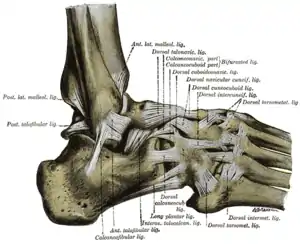

The ligaments of the foot from the lateral aspect (anterior tibiofibular ligament labeled at center top) | |

Lateral view of the human ankle | |